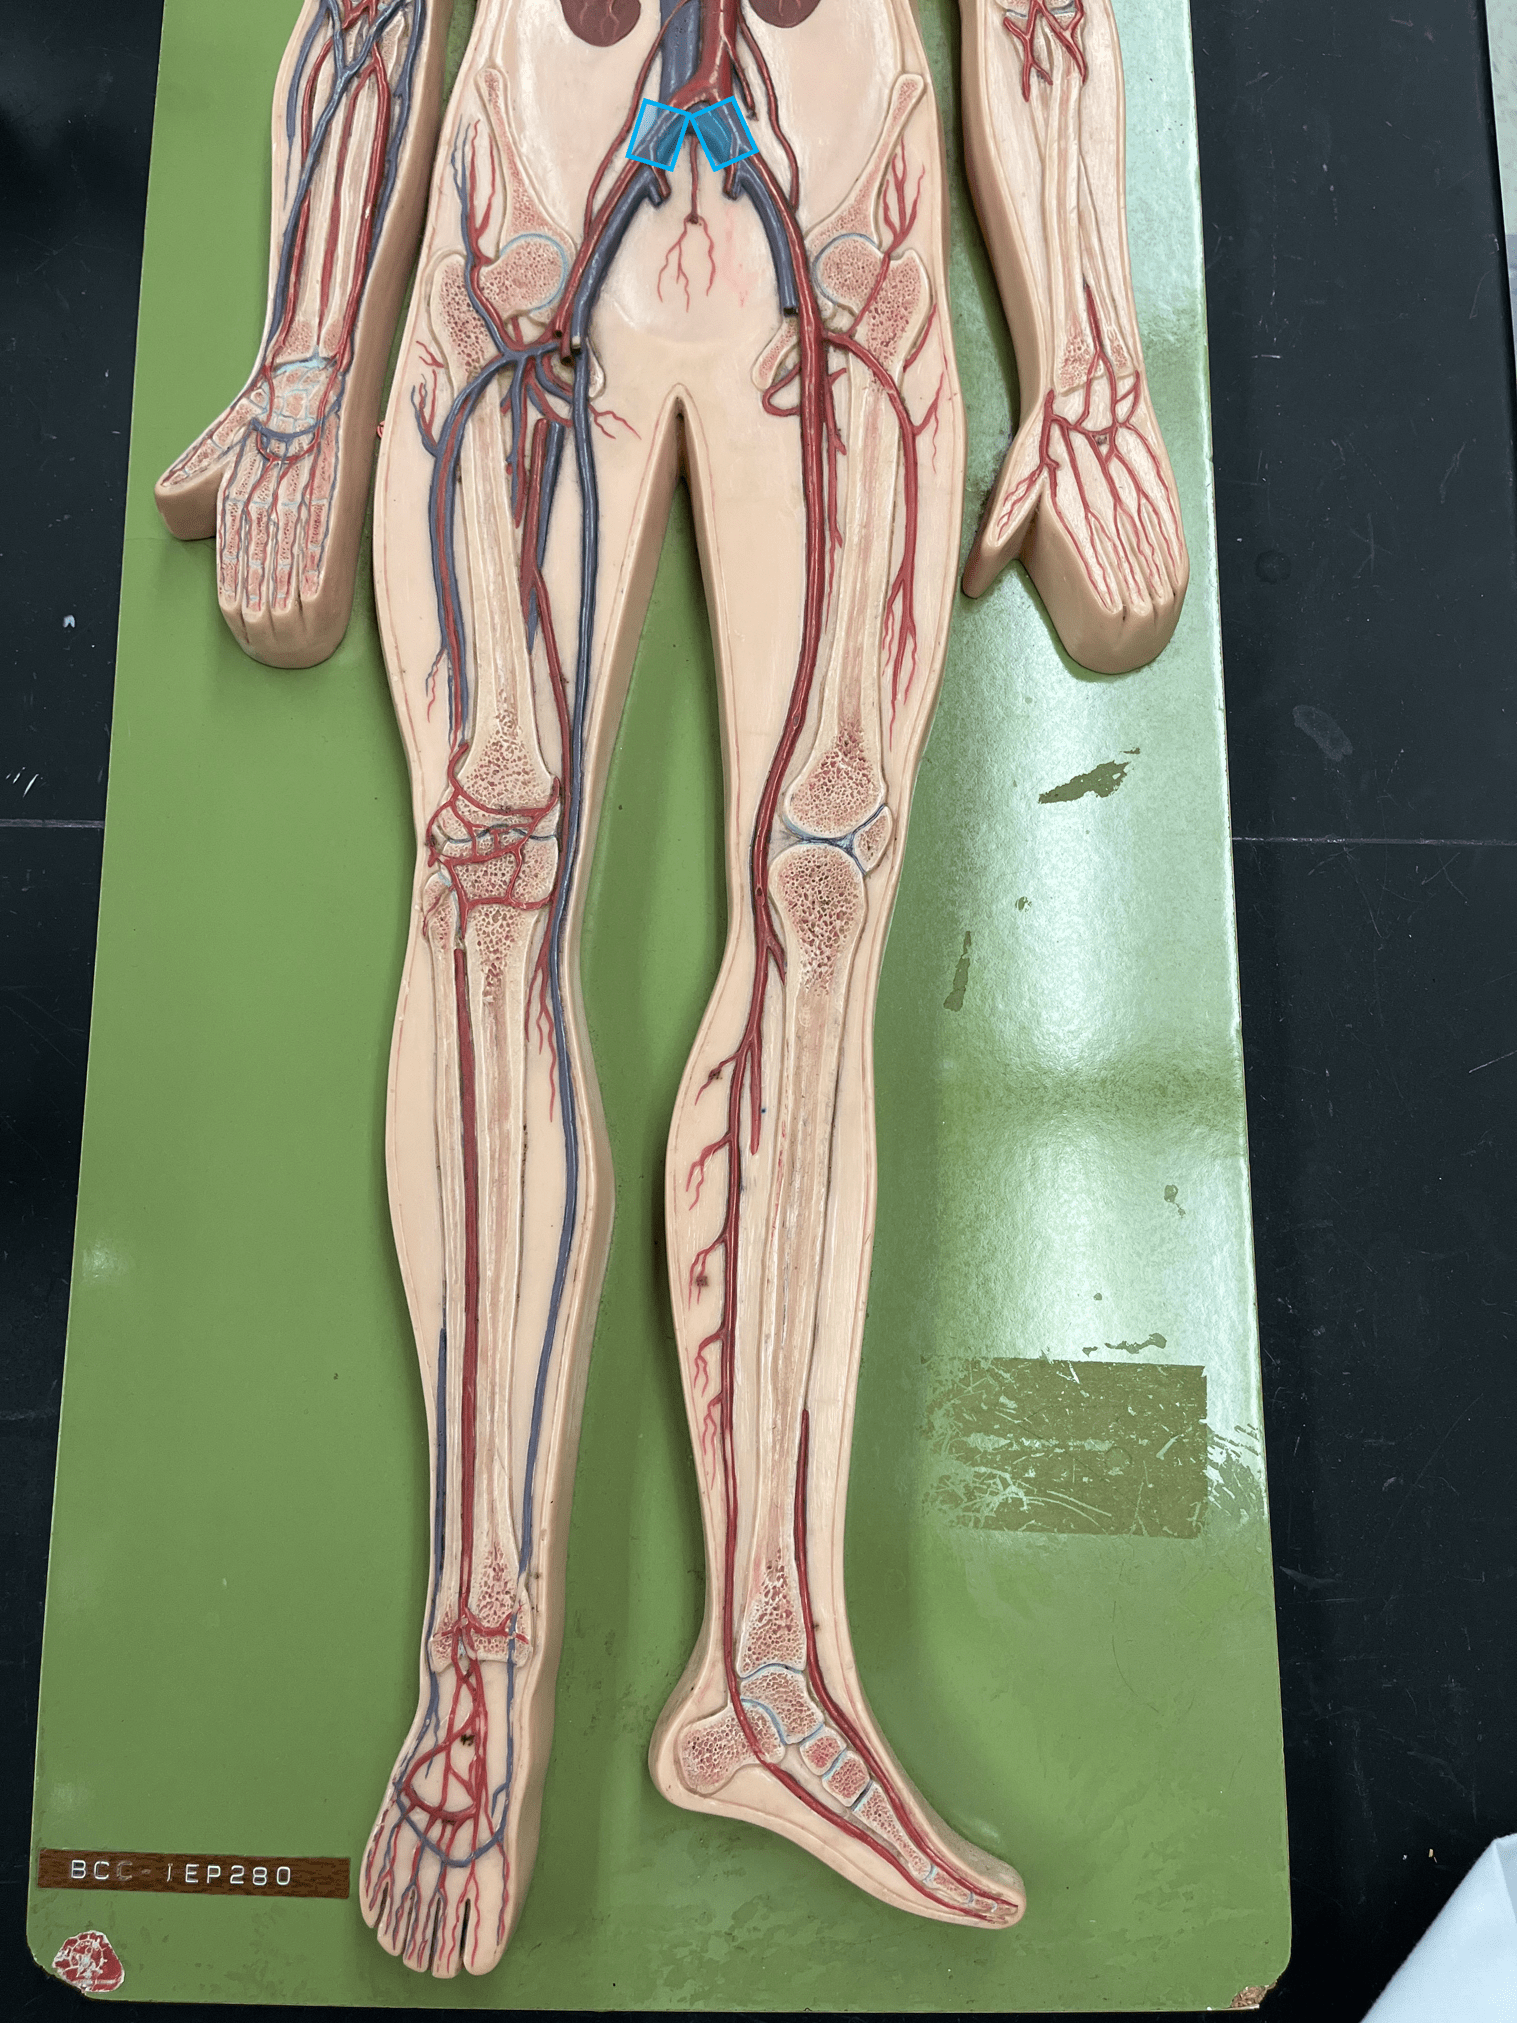

• Found between the tunica externa and tunica media.

11

New cards

endothelium

• Originates from the brachiocephalic trunk (R.) or the aortic arch (L.).

• Supplies the head and neck through its branches.